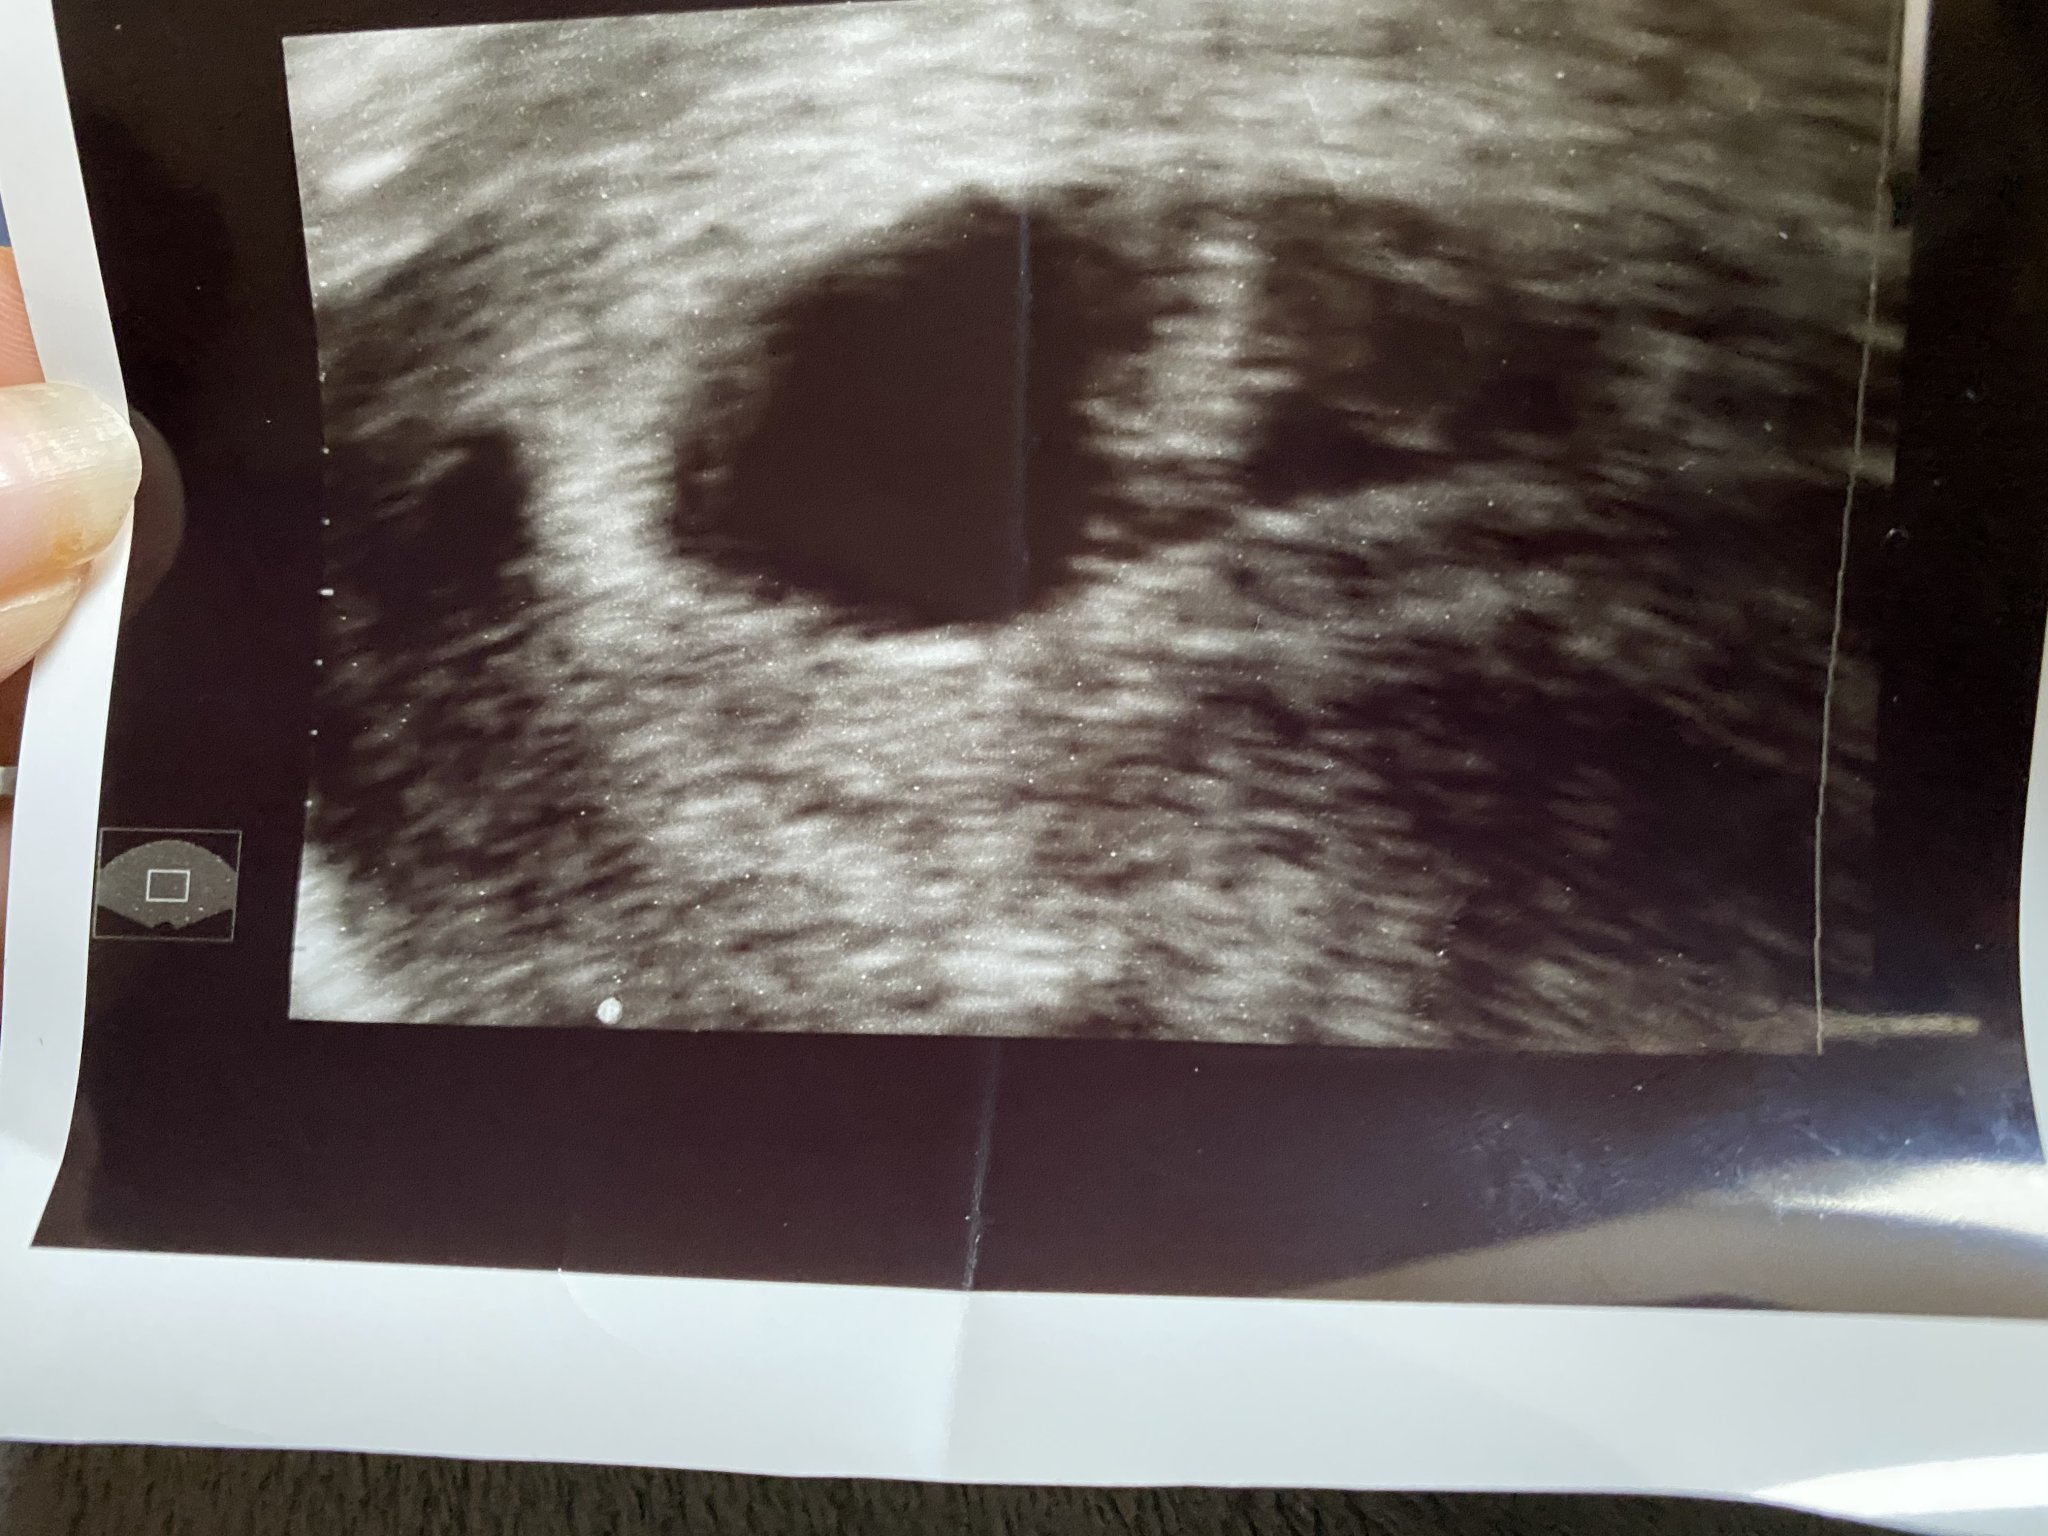

Здравейте, това е снимка в началото на 4г.с. Лекарят каза, че “има нещо”, дори ми посочи, но нищо не виждам?! Някоя от вас имала ли е подобна снимка?